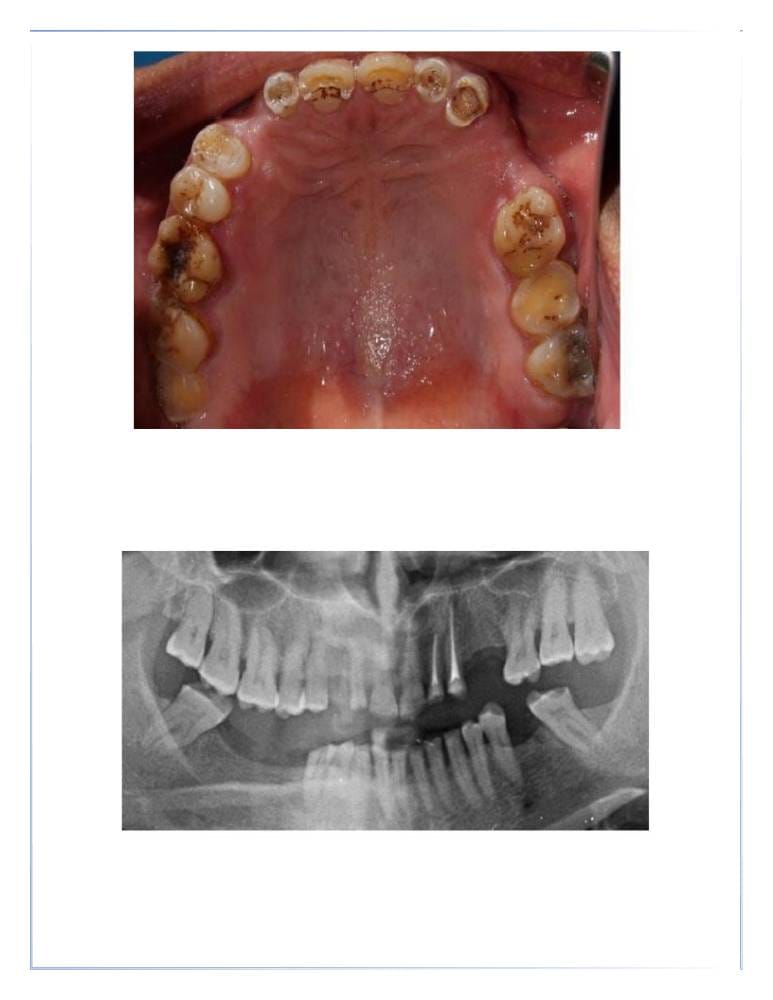

- علاج التسوس : من خلال الحشوات التجميلية.

علاج العصب (علاج الجذور)

- إزالة العصب الملتهب أو المتضرر.

- تنظيف وحشو قنوات الجذر لمنع الإصابة بالعدوى مرة أخرى.